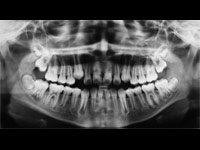

Las radiografías dentales pueden ayudar a predecir fracturas